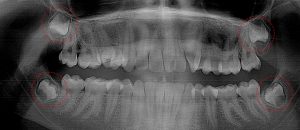

This 19 year old patient has all four 3rd molars present (circled). Only the upper left 3rd molar has fully erupted. The lower left 3rd molar is partially exposed and decaying while the lower right soft tissue impacted, both requiring extraction. Note the double crown on the upper right third molar.